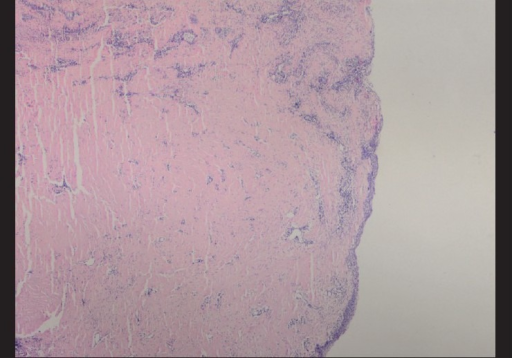

- 조직검사: 아밀로이드 유사 fibrin 침착